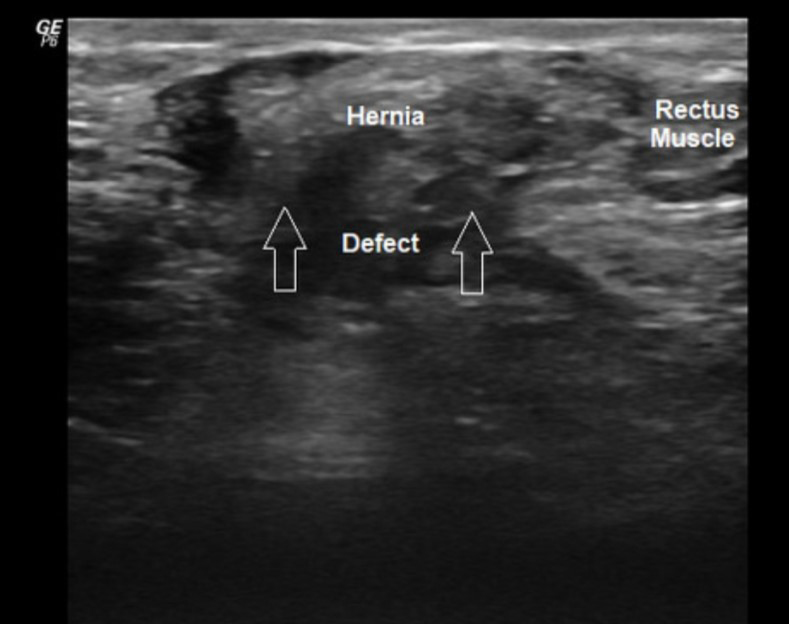

Fig. 1.Superficial soft tissue ultrasonography showing bulging in Pfannensteil incision site.

Radiologic workup including US, CT or MR imaging has always been used for

definitive diagnosis of hernia [28, 29, 30]. However, since majority of our patients

had significant bulging at their suprapubic area, radiology often provided us

with a road map offering guidance in operative planning and also raised awareness

of possible pitfalls that could occur during surgery. We usually combined soft

tissue US (90%) with at least one of the contrasted pelvic CT (70%) or MR

(30%) scan. Therefore, in our series, there was no important morbidity such as

bowel injury requiring suture raphy or diverting stoma. Moreover, knowing the

anatomic structures and adhesions between the fascia and bowel loops or

pre-placed mesh in complicated cases helped us decide on the type of dissection

or surgery. Although there are many publications reporting clear advantages of